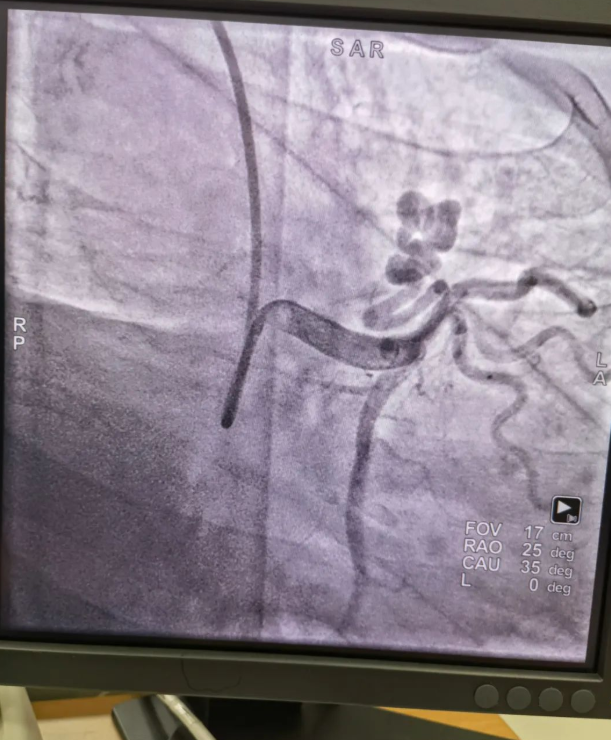

不久前,來自新疆的患者石先生去年至今反復(fù)胸悶、氣短、胸痛,就診于新疆某院,懷疑“冠心病”,住院行冠狀動脈造影術(shù),石先生造影提示“冠狀動脈肺動脈瘺”,而他并非“冠心病”,所以給予的“冠心病”治療,效果不佳。出院后仍反復(fù)出現(xiàn)胸痛、胸悶、氣短等癥狀,經(jīng)親友介紹了解到西安國際醫(yī)學(xué)中心醫(yī)院心臟病醫(yī)院心臟內(nèi)科二病區(qū)曾廣偉主任,多年來潛心研究心臟病介入治療,成功主刀救治了許許多多高危復(fù)雜病例,尤其是在先心病及結(jié)構(gòu)性心臟病封堵,以及冠心病、心律失常射頻消融及起搏治療等方面積累了豐富的診療經(jīng)驗。

此病例罕見,在曾廣偉從醫(yī)18年生涯里曾碰到有2個印象深刻的病例,患者分別是53歲和66歲,當(dāng)時建議患者入院進(jìn)行動脈瘺的封堵術(shù),但患者和家屬考慮到這個手術(shù)案例極少,風(fēng)險也高,均未接受手術(shù)治療建議,只是能采取藥物保守治療,出院后隨訪得知患者癥狀緩解效果不佳,后來在隨訪中也與53歲患者失去了聯(lián)系,而66歲患者因冠狀動脈肺動脈瘺出現(xiàn)反復(fù)心衰,在當(dāng)?shù)蒯t(yī)院藥物治療,短短2年時間,患者因為動脈瘺未及時手術(shù)失去了生命。所以此次患者石先生到訪,曾廣偉主任在詳細(xì)掌握病例資料基礎(chǔ)上,果斷建議進(jìn)行動脈瘺的封堵術(shù)治療,為了提高手術(shù)成功率和精準(zhǔn)度,曾廣偉主任搜集相關(guān)診療資料,反復(fù)推演論證,經(jīng)過相當(dāng)充足的準(zhǔn)備工作,于5月18日成功進(jìn)行了封堵手術(shù),完全堵上了瘺口。

患者術(shù)后第2天,已經(jīng)沒有明顯的胸悶、氣短、胸痛等癥狀,目前身體狀態(tài)良好。本次手術(shù)曾廣偉主任及其團(tuán)隊,采取從右手臂一根血管進(jìn)入,并在2小時之內(nèi)完美封堵,創(chuàng)口小,痛苦小。手術(shù)雖然難度大、風(fēng)險高,相關(guān)案例也少,但是曾廣偉主任主刀即在巔峰,這樣一臺完美的手術(shù)靠的不是運(yùn)氣,是豐富的臨床手術(shù)經(jīng)驗,扎實的專業(yè)知識儲備,以及對醫(yī)療事業(yè)的孜孜追求。

冠狀動脈瘺是指冠狀動脈與心腔、冠狀靜脈、肺動脈等的異常連接,是一種少見的先天性心臟病,發(fā)病率為1.3%。而冠狀動脈肺動脈瘺是冠狀動脈與肺動脈之間產(chǎn)生的一種血管性瘺口,導(dǎo)致冠狀動脈里的血液流入肺動脈里,使冠狀動脈里血液流量減少,出現(xiàn)心肌供血不足,冠狀動脈肺動脈瘺會使患者出現(xiàn)胸部疼痛、胸悶、呼吸困難、頭暈、乏力等一系列癥狀,隨著疾病不斷進(jìn)展,可引發(fā)心功能的障礙和心肌缺血,肺動脈會逐漸形成肺動脈高壓,還可能導(dǎo)致動脈瘤的破裂,甚至威脅病人的生命安全,所以早期發(fā)現(xiàn)和治療冠狀動脈肺動脈瘺,對病人的預(yù)后改善具有重要的意義。